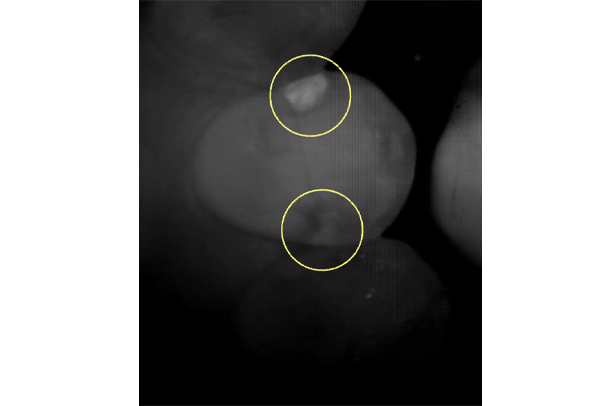

初診時バイトウィングデンタル

レントゲンだとちょっと虫歯が怪しいくらいに写っている。これだけだと確定診断としては、判断材料が少ないと考えられる。

黄色丸の部位が、他の部位と違って白く抜けがあるのがわかります。これがNIRI機能による虫歯の診査です。

この機能のおかげで、歯と歯の間の見つけにくい虫歯がよくわかるようになってきました。